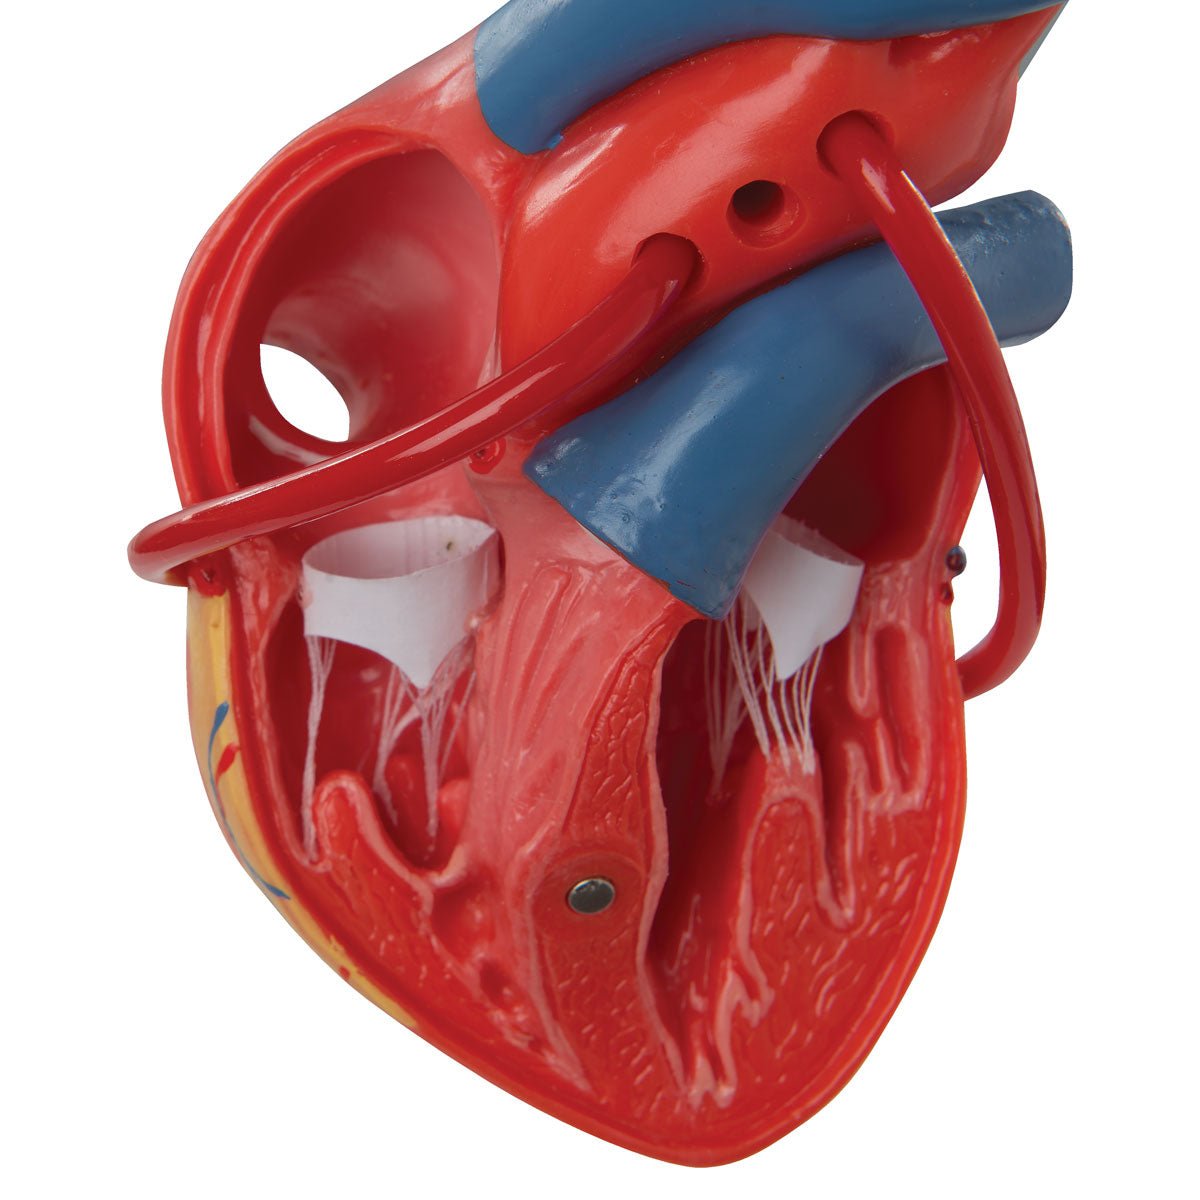

Anatomical models

Selling anatomical models is the mainstay of eAnatomi, although we also spend a lot of resources developing our own anatomical materials such as posters. Anatomical models are used for various purposes and can show both defined tissues, organs and organ systems. Are you looking for a simple model of bone tissue or perhaps an advanced torso model based on MRI technology, you can find it all at eanatomi.com.